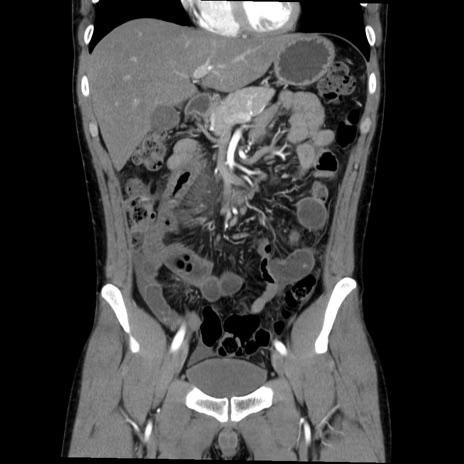

症例36(冠状断像)

【症例】20歳代 男性

【主訴】心窩部痛

【現病歴】今朝より上腹部痛あり。一旦軽快していたが再度出現したため救急要請。昨日夕に白身の魚を含む刺身を食べた。

【身体所見】BP 136/89mmHg、HR 74/min、BT 37.0℃、腹部:膨満、軟、心窩部に圧痛あり。反跳痛なし、筋性防御なし、腸雑音やや亢進あり。

【データ】WBC 17700、CRP 0.48